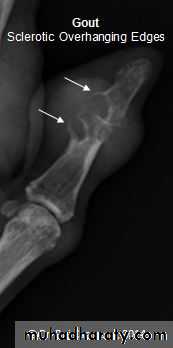

GOUT

• Heterogeneous group of entities characterized by recurrent attacks of arthritis secondary to deposition of sodium urate crystals in and around joints.• *90% of patients are male

• Radiographic features

• *Lower extremity > upper extremity; small joints > large joints

• * First MTP is most common site

• * Marginal, peri articular erosions: overhanging edge

• * Erosions may have sclerotic borders

• * Joint space is preserved